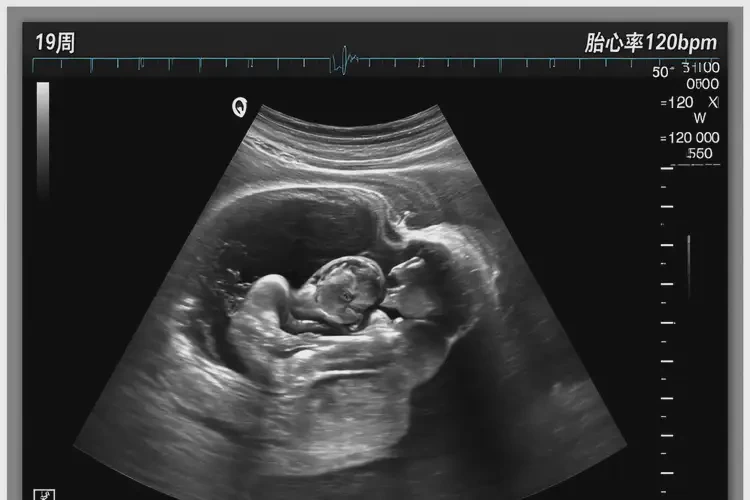

孕19周4天胎心率167還要保胎嗎(圖1)

孕19周4天胎心率167還要保胎嗎(圖2)

孕19周4天胎心率167還要保胎嗎(圖3)

孕19周4天胎心率167還要保胎嗎(圖4)